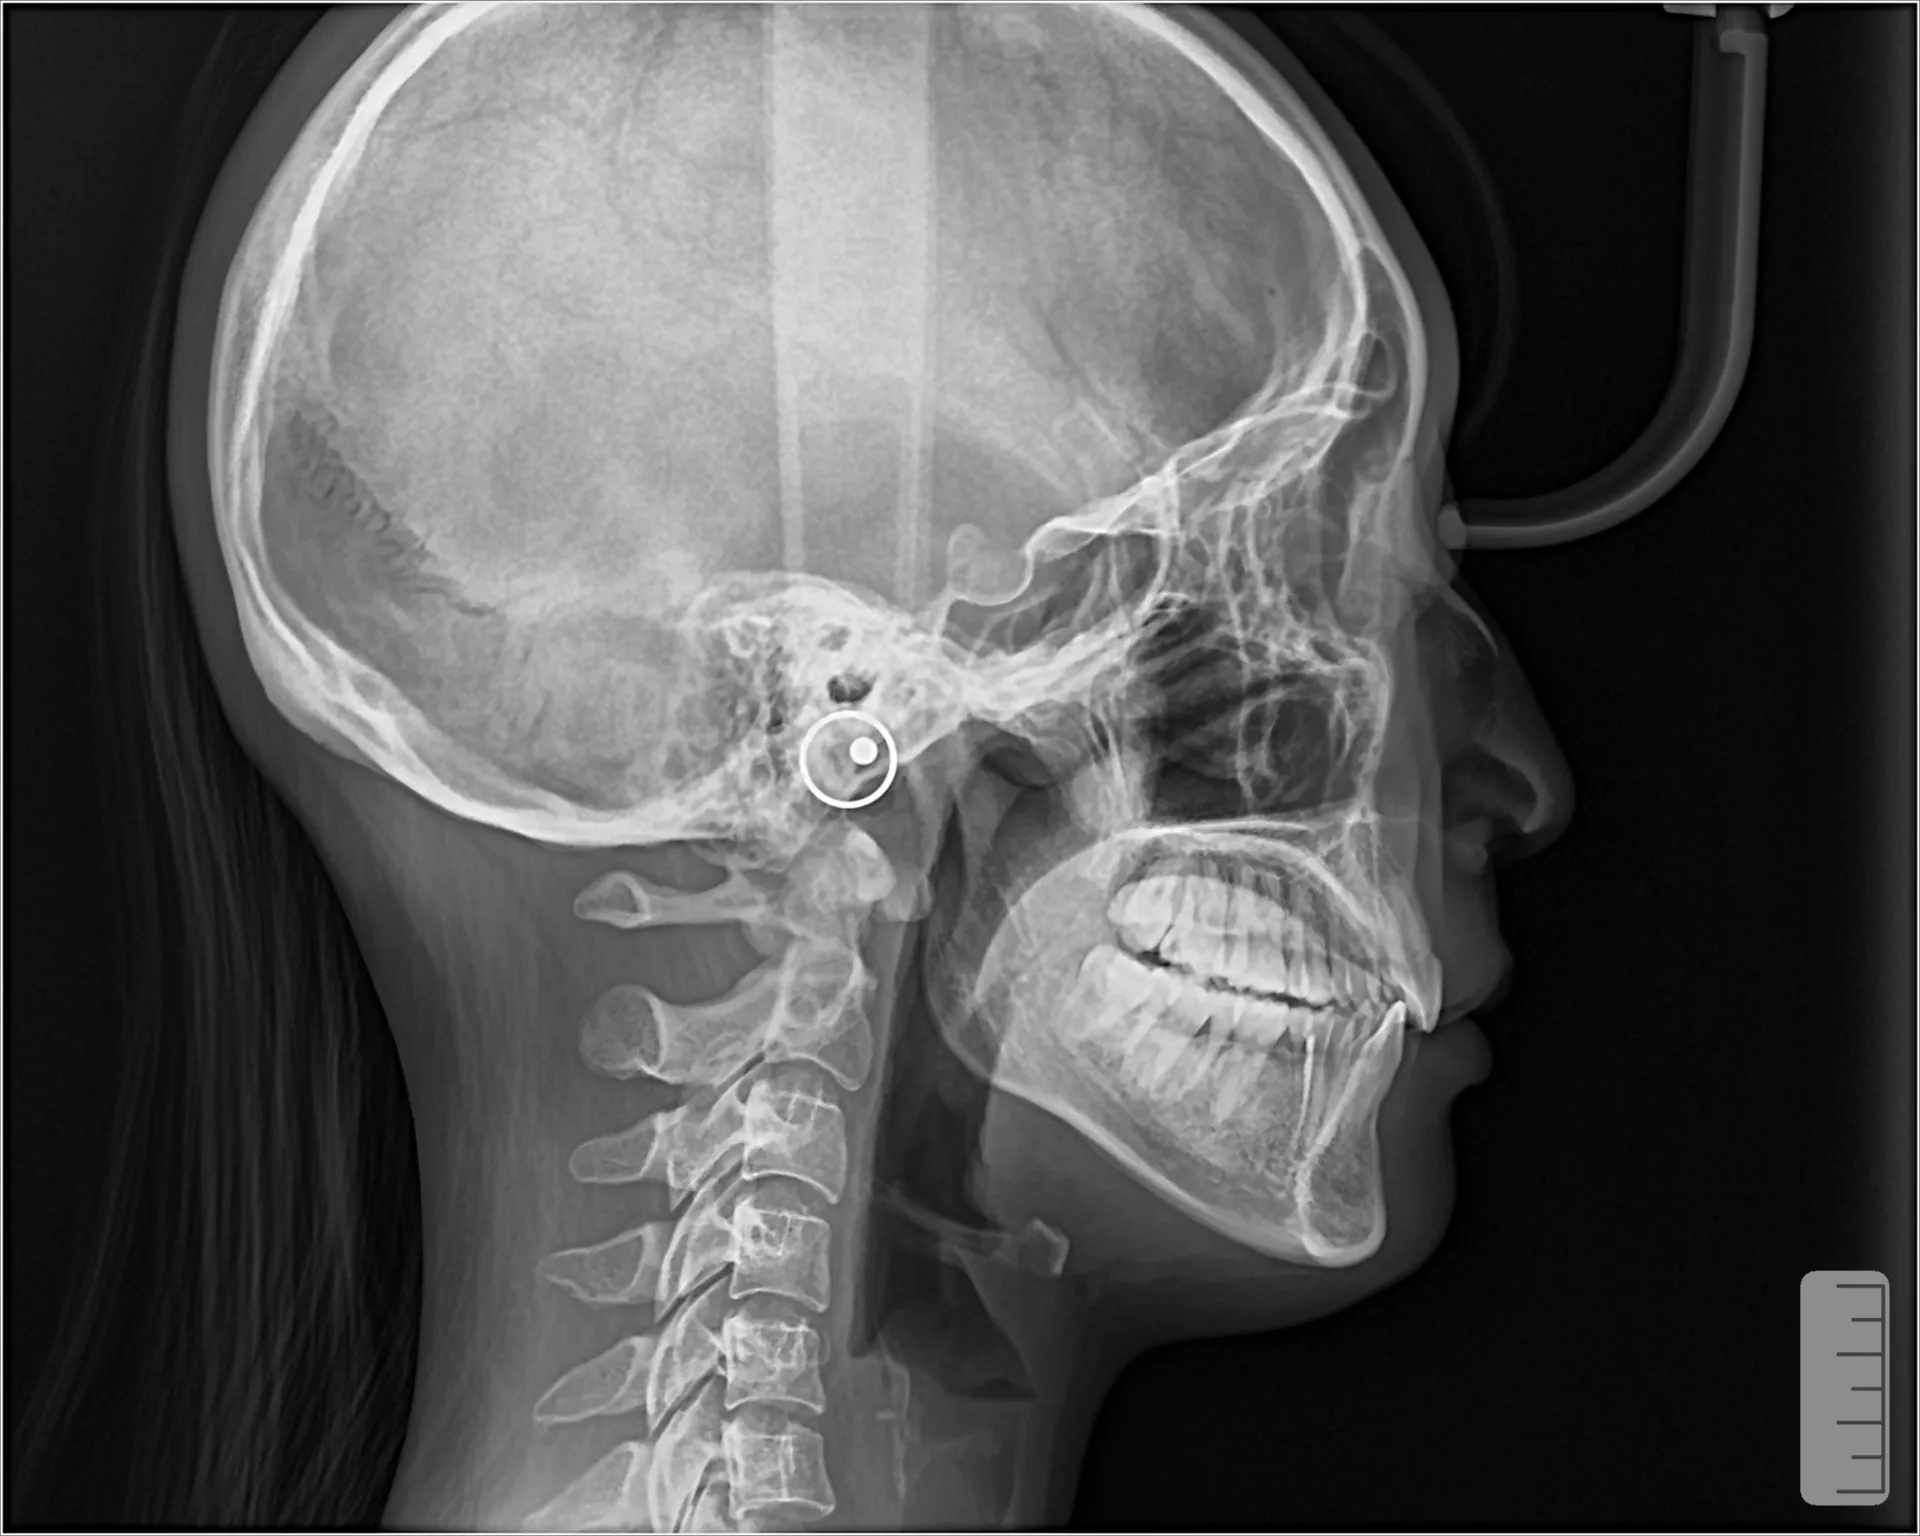

矯正治療では 歯の位置が変わると唇の位置も変わる ため、Eラインが変化します。

① 出っ歯(上顎前突)の場合

前歯を後ろに下げると

唇が後退

口ゴボ改善

Eラインが整う

② 口ゴボ(上下顎前突)

上下の前歯が前に出ている状態。

矯正で

上下前歯を後退

口元が引っ込む

横顔がスッキリ